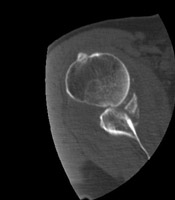

DGlenoid Fracture |

Glenoid fractures are usually the result of blunt trauma to the upper extremity. Subtle fractures can be difficult to detect on conventional radiographs; CT may be required for full diagnosis. A special glenoid fracture is termed the Bankart fracture. This consists of fracture of the inferior lip of the glenoid during anterior shoulder dislocation.